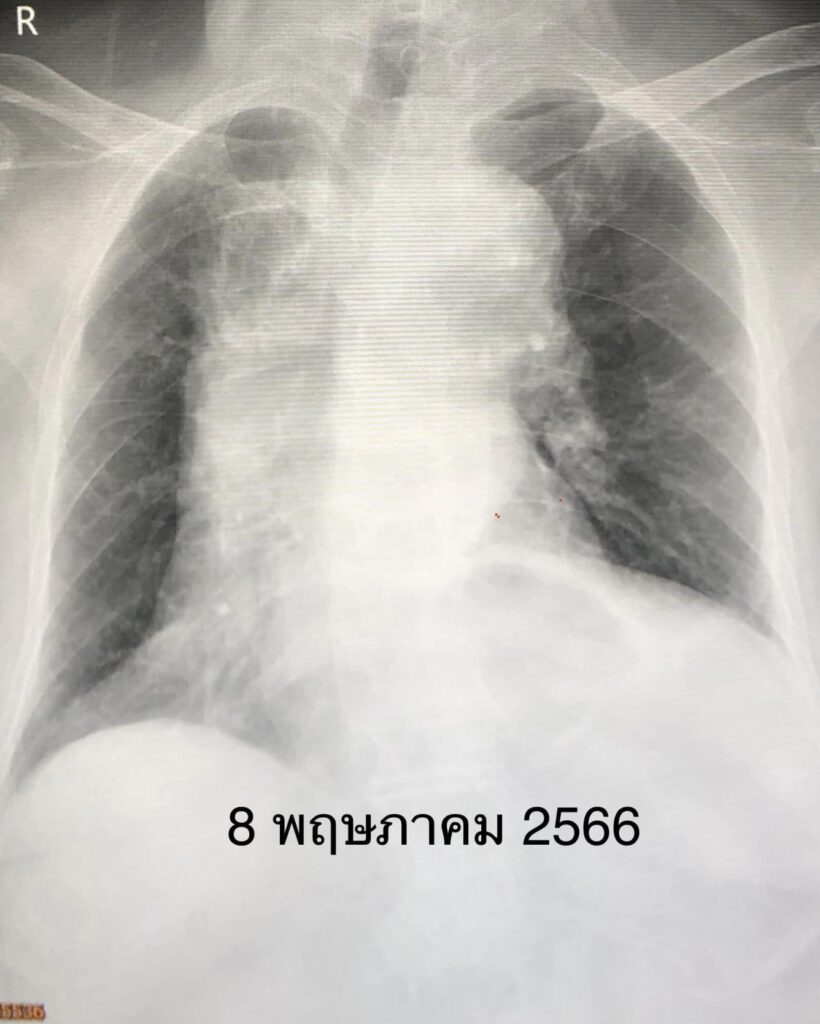

เริ่มไอ 2 วัน เหนื่อยเล็กน้อย ไม่มีไข้ ไม่เจ็บคอ ไม่มีน้ำมูก ตรวจ ATK บวก ติดเชื้อไวรัสโควิดครั้งแรกจากคนเฝ้าและลูกสาวที่อยู่ในบ้านเดียวกัน ผู้ป่วยรู้ตัวดี พูดได้ ไม่มีไข้ เอกซเรย์ปอดปกติ (ดูรูป) รับเข้านอนในโรงพยาบาลวันที่ 10 เมษายน 2566 เริ่มยาต้านไวรัสเรมเดซิเวียร์ฉีดเข้าเส้นเลือด